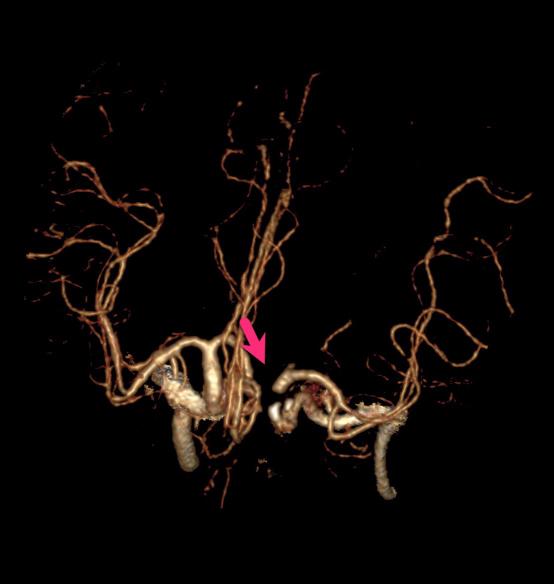

58岁的李大哥1周前有晕倒病史,但是没有到医院系统的治疗。发病前5个小时被人发现说不出话,右侧肢体不能活动。在我院神经内科急诊完善头颈部动脉CTA+CTP提示左侧大脑半球大片缺血带(图1)。是怎么回事呢?细心的血管介入科医生经过认真的分析图像,发现李大哥左侧颈内动脉存在的一个非常局限性的闭塞(图2、3),由于该段血管迂曲的走行在颅骨内不宜被发觉。得益于我院卒中团队的丰富经验,患者很快经绿色通道送至导管室准备手术。

图2

图3